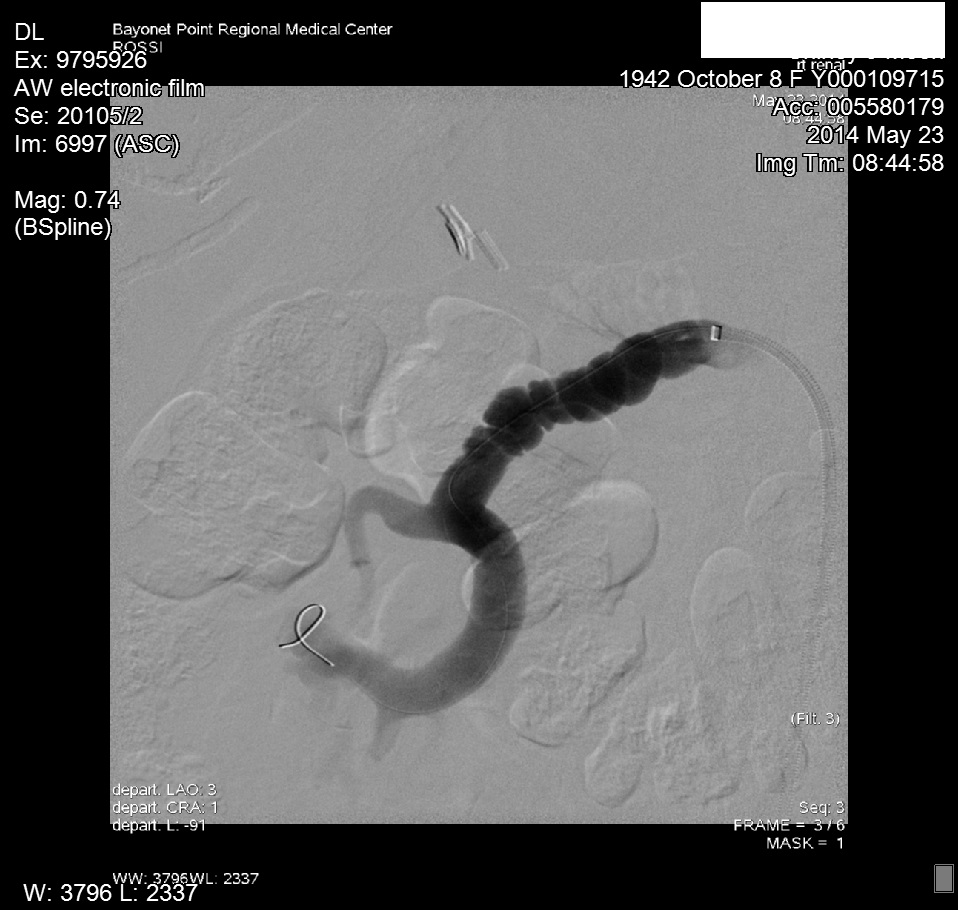

Upon obtaining the abnormal doppler findings, our interventional cardiologist performed an abdominal angiogram with selective bilateral renal arteriography. The angiogram demonstrated diffuse right renal artery haustra consistent with FMH. As well, abnormal retograde filling of the right renal vein and IVC was noted, and consistent with an AV fistula within the right renal artery helium (Figure 4). The left renal artery was normal on preliminary imaging, but remained suspect. Upon IVUS (Intra Vascular Ultra Sound) imaging, a significant (20mm) gradient was noted within the left distal renal artery.3 Bilateral cutting balloon angioplasties were performed and the patient was then sent to CPRU for recovery (Figure 5 & 6).

Figure 4 CTA of RRA FMD.

Figure 5 Angiogram images of RRA FMD.

Figure 6 Angiogram images of RRA FMD.